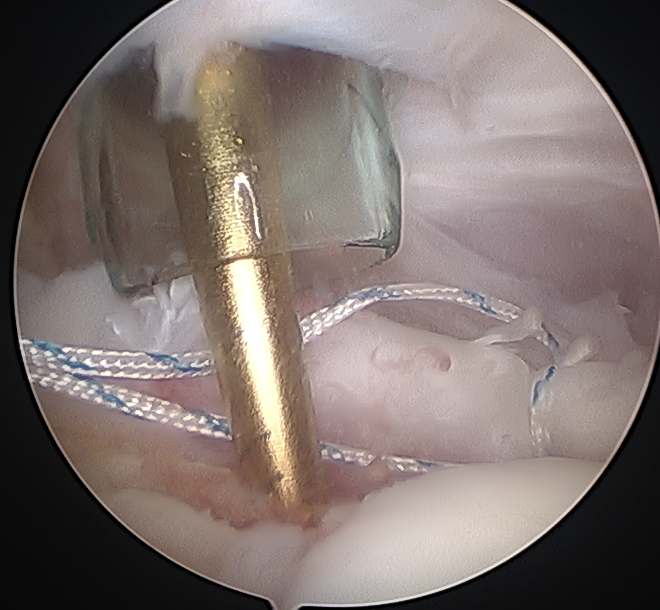

- tag biceps tendon with high strength suture and release

Tag biceps and release